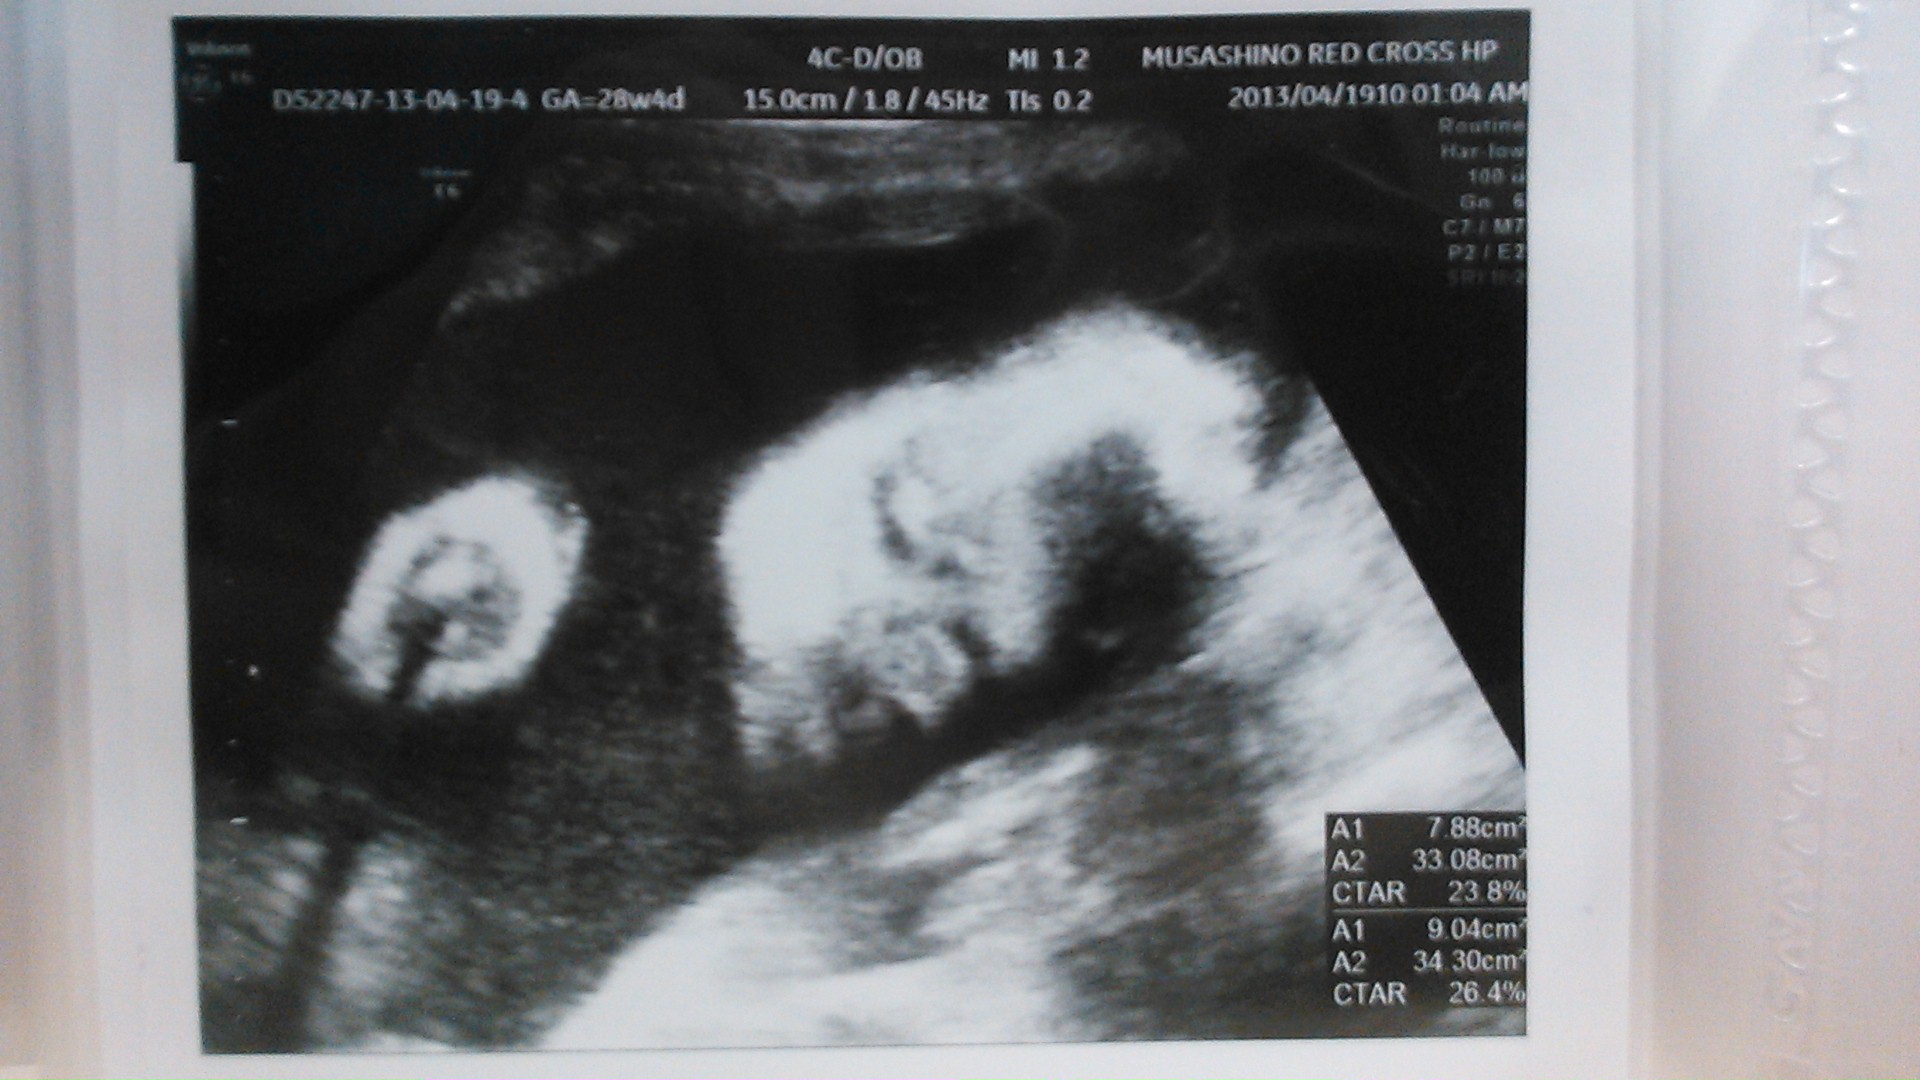

echo